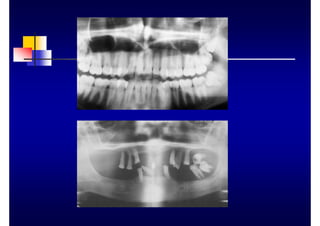

„ Utilidad

„ diagnóstico

„ pronóstico

„ tratamiento

„ Técnicas

„ periapicales cono largo

„ panorámicas

„ aletas de mordida

„ serie radiográfica

„ Limitaciones

„ bolsas periodontales

„ destrucción ósea V y L

„ tejidos blandos

„ gingivorragia

„ movilidad dentaria